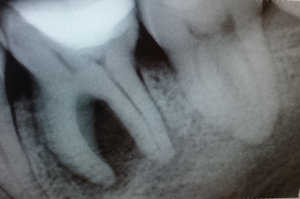

У меня зуб болит. Я его лечила 3 года назад. Мне поставили штифт в декабре 2015, он опять заболел, сделали снимок, оказалось, что он был плохо пролечен. Сняли пломбу, смогли пройти только один канал, во втором канале материал, третий мне врач не смог пройти (инструмент упирался в десну). Тогда еще врач сказал, что этот зуб только удалять, я не согласилась на удаление и мне его просто перекрыли пломбой, теперь опять побаливает.

Как думаете, нужно удалять или его еще можно спасти?

В зубе имеется перфорация, к сожалению, такой зуб спасти и сохранить невозможно.